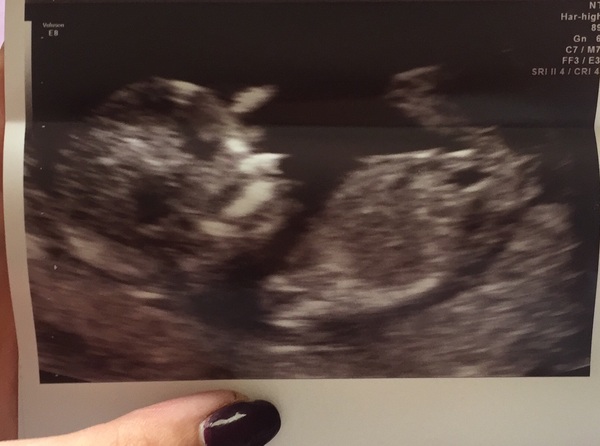

summerskittles91 · 20/09/2016 20:22

Here is scan pic from earlier! Smile

April 2017 #4 More baby scans, less morning sickness!

Love it summerskittles, I'm so nervous about mine tomorrow Hmm Hope to god it's all ok

These scan pics are great! Proper real babies! Hoping that will help it to feel real, rather than just like I have a perpetual hangover.

Amazing summerskittles (nice nail varnish too! Grin ) - congrats on all the great scans today, especially after your scare choccy